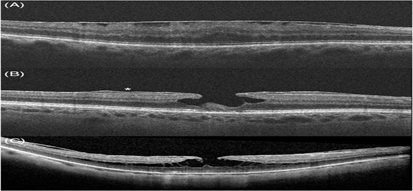

Hình ảnh trên OCT của màng trước võng mạc và các khái niệm có liên quan: A- màng trước võng mạc, B- lỗ lớp hoàng điểm cùng với tăng sinh trước võng mạc (dấu sao), C- tách lớp VM

Sự thay đổi từ phương pháp soi sinh học bằng đèn khe truyền thống sang phương pháp chụp ảnh cắt lớp võng mạc thế hệ SD-OCT đã dẫn đến nhu cầu sửa đổi các định nghĩa lỗi thời về các bệnh võng mạc vốn có thể khó phân biệt với nhau. Giờ đây các bác sĩ có thê phân định chính xác các tổn thương sau đây với nhau:

Sự nhất trí về các định nghĩa cho các tình trạng võng mạc này đã làm giảm bất đồng trong chẩn đoán của các bác sĩ và thúc đẩy áp dụng thêm nhiều công nghệ mới để điều trị ERM.